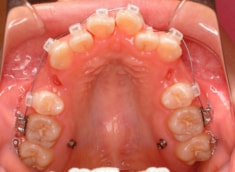

治療開始時